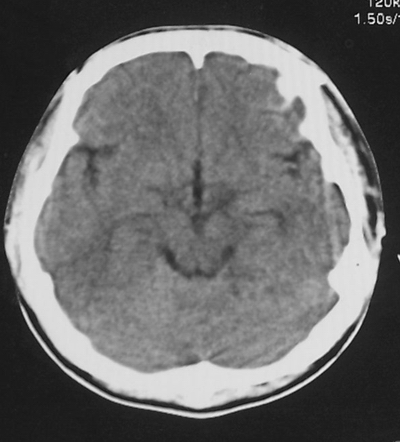

患者、男、18y,头痛5天入院。

左小脑、右丘脑区低密度影,无明显强化及占位表现,男18y,先考虑脑部炎性病变,如脑炎、血行播散性感染等,建议结合临床如脑脊液检验。

单独看左侧小脑半球的不规则形囊性低密度灶,从发病部位、年龄以及无强化、无占位效应的特点可以考虑毛细胞瘤型星形细胞瘤。同样,如果单独看右侧丘脑的近圆形低密度,也可以考虑囊变形星形细胞瘤。只是胶质细胞瘤一般为单发直接浸润、蔓延生长,而不是在脑内同时出现多个病灶,且瘤周没有一点儿水肿,暂时不予以考虑。

左侧小脑半球及右丘脑低密度影,考虑  1、脑梗塞灶. 2、占位性病变,建议作mri检查

左侧小脑半球及右丘脑低密度影,还是在做个mri较为妥当。